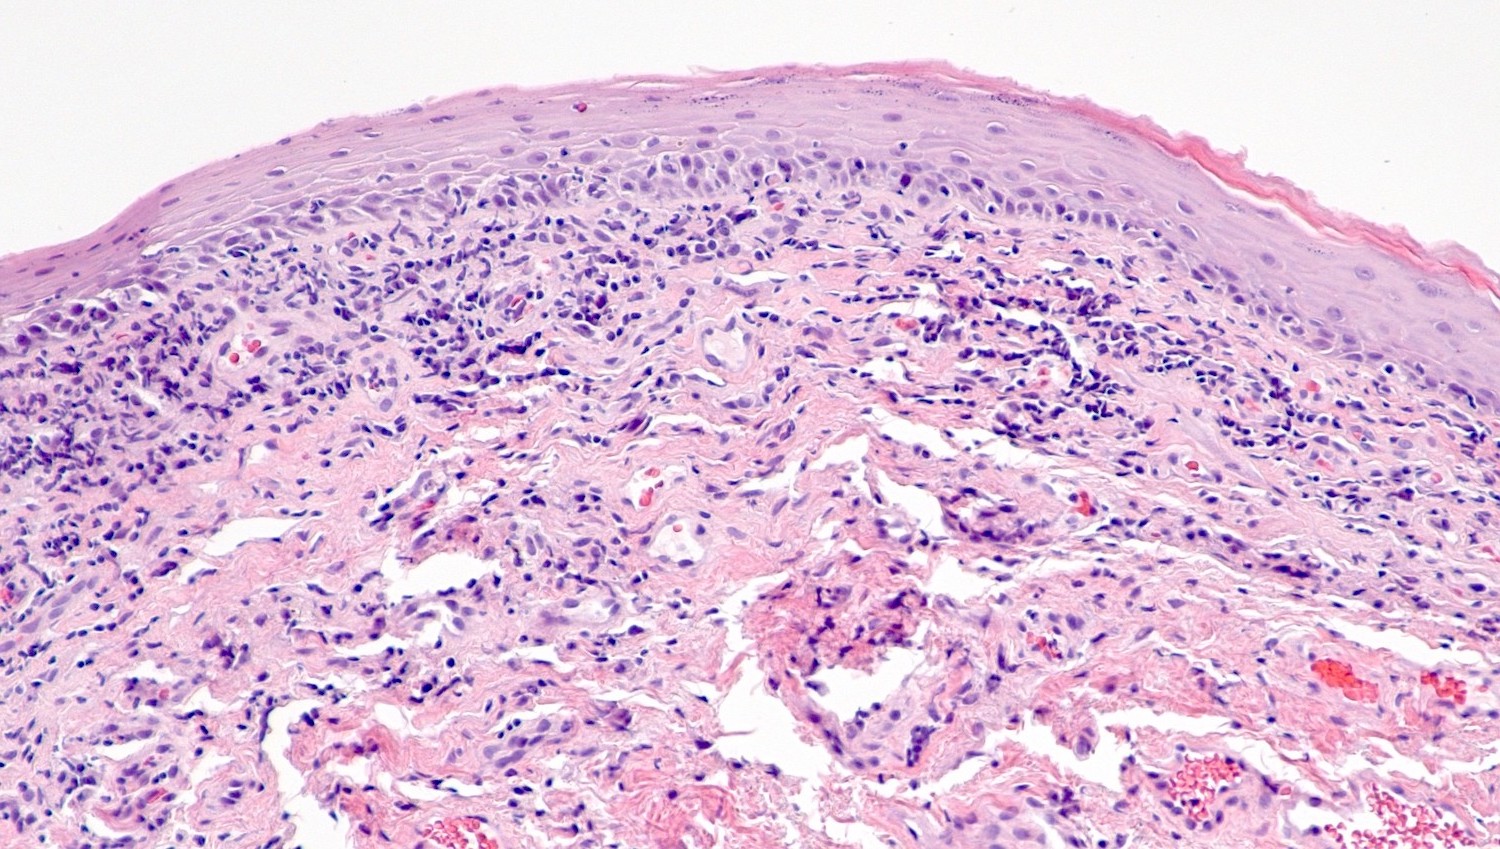

Microscopic (histologic) description

- Vacuolar interface reaction pattern in conjunction with dermal sclerosis (homogenized and hyalinized eosinophilic collagen bundles) of any thickness intervening between inflammatory infiltrate and epithelium or vessel walls (Mod Pathol 1998;11:844)

- Early lesions show only the inflammation and no or minimal fibrosis (inflammatory phase); the histopathological findings at this stage of disease development are not diagnostic

- Severe hyperkeratosis; thin epidermis, loss of rete pegs, basal cell degeneration, homogenized band of dense fibrosis at papillary dermis, upper dermal edema, band-like chronic inflammation

- In early stages, findings are subtle and often more prominent in adnexal structures than in interfollicular skin; adnexal structures show acanthosis, luminal hyperkeratosis and hypergranulosis

- Early dermal changes are homogenized collagen and wide ectatic capillaries in dermal papillae immediately beneath basement membrane

- Superficial dermal collagen may be wire-like with lymphocyte entrapment (J Cutan Pathol 2015;42:510)

- Lymphocytic infiltrate can be sparse or dense, lichenoid or interstitial with epidermal lymphocyte exocytosis

- Erosions or ulceration can occur (J Low Genit Tract Dis 2021;25:255)

Microscopic (histologic) images